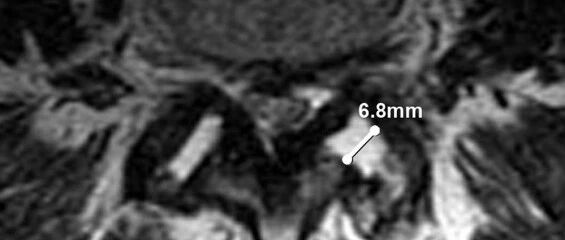

小关节积液>1.5mm提示退变性腰椎滑脱